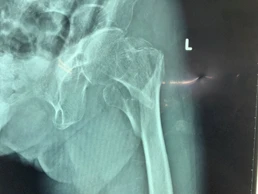

Kết quả chụp X-quang cho thấy xương đùi trái bà H. bị gãy nhiều mảnh. Ảnh: HÒA KHÁNH

Sau khi chụp X-quang, các BS kết luận đùi trái bà H. bị gãy nhiều mảnh xương kín. Các BS đã tiến hành phẫu thuật nối các mảnh xương gãy với nhau. Hiện cụ H. có thể sử dụng khung hỗ trợ để đi lại.